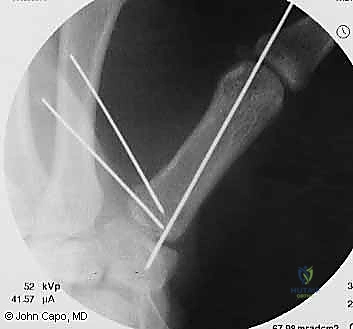

1. الرد المغلق والتثبيت عبر الجلد بالإبر (CRPP - Closed Reduction and Percutaneous Pinning)

هذا الإجراء هو الخيار المفضل لكسور "بينيت" التي يمكن إعادتها لمكانها بدون فتح جراحي كبير.

* الخطوات: يتم إجراء العملية تحت التخدير الموضعي أو الكلي. باستخدام جهاز الأشعة السينية المباشر في غرفة العمليات (C-arm Fluoroscopy)، يقوم البروفيسور هطيف برد الكسر إلى مكانه المثالي.

* بعد ذلك، يتم إدخال إبر معدنية دقيقة (K-wires أو Kirschner wires) عبر الجلد مباشرة لتثبيت قاعدة المشط الأول بالعظم المربعي، وأحياناً بالمشط الثاني لزيادة الاستقرار.

* الميزة: شقوق صغيرة جداً، ألم أقل، وشفاء أسرع. يتم إزالة هذه الإبر عادة في العيادة بعد 4 إلى 6 أسابيع.